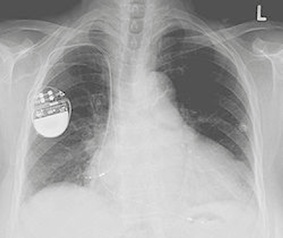

Od 60. let 20. století prodělala technologie kardiostimulátorů obrovský vývoj. Kardiostimulátory jsou menší, lehčí, pro nositele mnohem pohodlnější a jsou mnohem odolnější proti elektromagnetické interferenci (EMI). Skládají se z baterie a elektronických obvodů uložených v titanovém pouzdře. Pokud kardiostimulátor nedetekuje v pacientově srdci dostatečně silný elektrický signál, vyšle do srdečního svalu krátký elektrický proud o nízkém napětí. Přes 50 % implantovaných kardiostimulátorů dokáže upravit frekvenci vysílaných signálů podle fyzické aktivity pacienta (Allen, 2006).

Většina kardiostimulátorů je implantována při místním znecitlivění a umisťuje se pod klíční kost, mezi kůži a hrudní svalstvo. Z kardiostimulátoru vycházejí elektrody, které jsou zavedeny do srdce. Někdy je kardiostimulátor implantován do břicha a elektroda je umístěna na vnější stěně srdce (British Heart Foundation, 2005). Moderní kardiostimulátory jsou napájeny lithiumjodidovými bateriemi, které mají životnost 6–10 let. Filtry, které jsou součástí softwaru kardiostimulátoru, zajišťují velkou míru tolerance vůči EMI a další ochranu proti jejímu působení zajišťuje titanové pouzdro kardiostimulátoru (Allen, 2006). Tonks (2006) se vyjadřuje velmi skepticky, pokud jde o počet kardiostimulátorů, které jsou staženy jako vadné, a cituje statistické údaje o velkém počtu vadných přístrojů. Tonks se domnívá, že neexistují spolehlivé údaje o počtu kardiostimulátorů, které selžou kvůli vadným elektrodám, ani o počtu pacientů, kteří zemřou kvůli tomu, že jejich kardiostimulátor byl vadný. Britský Úřad pro kontrolu léčiv a zdravotnických výrobků (Medicines and Healthcare Products Regulatory Agency – MHRA, 2008) popisuje značný počet upozornění (Medical De vice Alerts), vydaných v letech 1997– 2007 kvůli vadným kardiostimulátorům, a to i od renomovaných výrobců. Vady se týkají selhání mikroprocesorů, nebezpečí selhání kardiostimulátoru, rychlé stimulace, k níž dochází, když je přístroj vypínán, a náhlé ztráty výkonu. V roce 2002 přiznal úřad MHRA problém s nedostatečným hlášením nežádoucích událostí týkajících se kardiostimulátorů a zdůraznil nutnost, aby mu technici a kliničtí pracovníci zabývající se kardiostimulátory nežádoucí události hlásili (MHRA, 2002). Fogoros (2003) uvádí, že všechny vady kardiostimulátoru se obvykle projeví brzy po jeho implantaci a mohou být zjištěny a napraveny dřív, než způsobí závažné komplikace. Symptomy, které mohou signalizovat špatnou funkci kardiostimulátoru: pacient se cítí slabý, unavený, zmámený, má závratě nebo ztrácí vědomí. V těchto případech by měl kontaktovat svého lékaře.

Ilustrační foto www.ulekare.cz

Ilustrační foto www.wikiskripta.eu